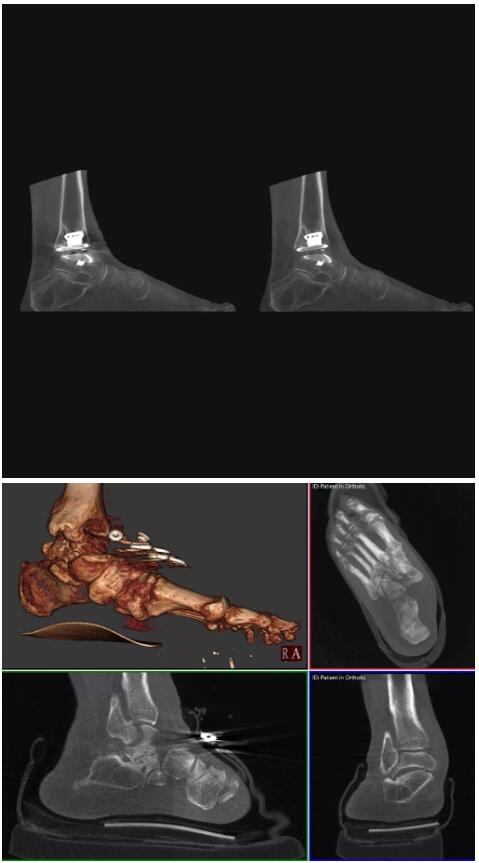

比如上面這款專用于足部和踝部掃查的CT成像系統(tǒng),患者在進(jìn)行CT掃查時(shí)只需要站在上面即可,雙腳站或者單腳站都可以,當(dāng)然,如果患者不是那么方便站著做完CT掃查,也可坐在上面。

這款CT掃查系統(tǒng)自帶屏蔽裝置,它的體積非常小,僅需要極小的空間即可,并不像常規(guī)CT那樣需要一間單獨(dú)的檢查室。此外,這種CT掃查的速度非常快,僅需30秒左右可以完成檢查,輻射劑量相對常規(guī)的CT要少許多,尤其適合醫(yī)院的骨科使用。

而患者站著做足部或者踝部做CT檢查還有個(gè)好處是,可以檢查患者在負(fù)重的情況下,骨關(guān)節(jié)的真實(shí)情況,而躺著做CT掃查時(shí)未必能看出來。負(fù)重CT掃查特別是對于受傷的運(yùn)動(dòng)員或者舞蹈員來說意義更大,能夠更準(zhǔn)確地評估傷情,幫助他們盡早復(fù)原。

以上介紹的CT均來自國外同一家公司,這些CT均配置了可視化軟件,可以進(jìn)行切片、3D重建以及大型CT附帶的所有典型的操作功能。

以下是這些“特立獨(dú)行”的CT所拍出來的圖像: